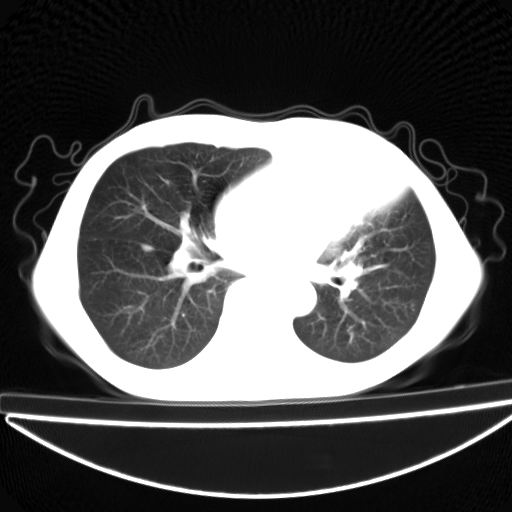

以下是引用杀毒软件在2009-4-28 17:58:00的发言:[br]考虑----左肺慢性肺脓肿形成继发上叶含气不良---抗炎后复查---待排肿瘤所致[br][br][本贴已被 杀毒软件 于 2009-4-28 18:01:26 修改过]